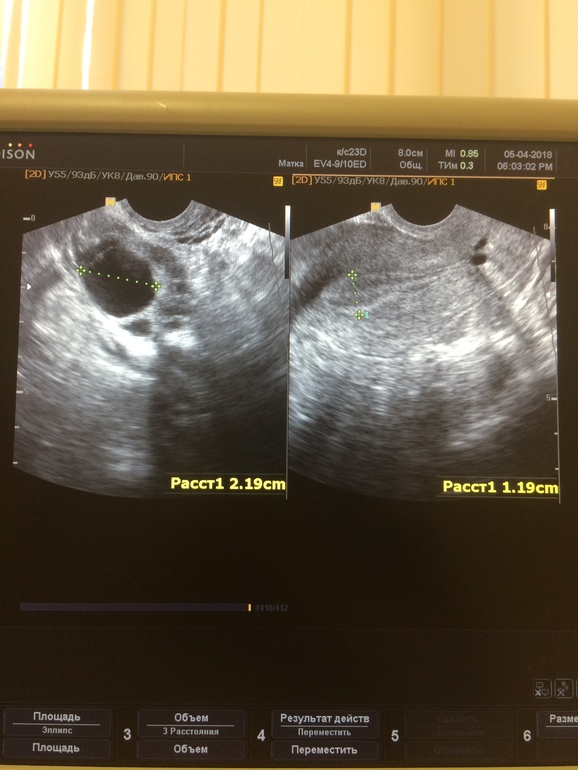

Вчера, на 11дц, был ДФ 21мм и эндометрий 11мм

Вот фото вчерашнего фоллика.